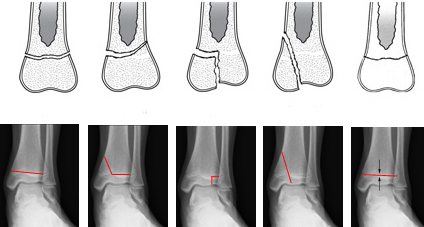

В зависимости от типа смещения костей переломы голеностопа бывают:

- Наружно-ротационными – такой вид перелома характеризуется поворотом кости по спирали, в этом случае он зачастую осложняется смещением сустава в наружную сторону или назад, а также может произойти отрыв внутренней лодыжки.

- Абдукционными – при этом типе травмы основной удар приходится на малоберцовую кость, и перелом или трещина появляется в поперечной проекции.

- Аддукционными – такие переломы сопряжены с резким подгибом ноги внутрь, при этом страдает и пяточная кость, и внутренняя лодыжка.

- Перелом со сдавливанием по вертикали – этот тип возникает от резкого удара стопы, например, при падении с высоты. В данном случае стопа перемещается вверх и вперед.

В зависимости от тяжести поражения, переломы голеностопного сустава бывают со смещением костей и без смещения. Говоря о травмах лодыжки, стоит отметить, что нарушение целостности сустава в этой части редко происходит с простым смещением костей – они еще и прокручиваются вокруг своей оси на определенный градус. Такие повреждения могут усложниться и образованием патологического угла одной кости по отношению к другой. Переломы со смещением и вывихом голеностопного сустава в лечении наиболее сложны, поскольку кость необходимо вернуть в прежнее положение, а уже потом говорить о сращении ее частей. Правильно поставленная кость – залог успешного лечения перелома голеностопа со смещением.